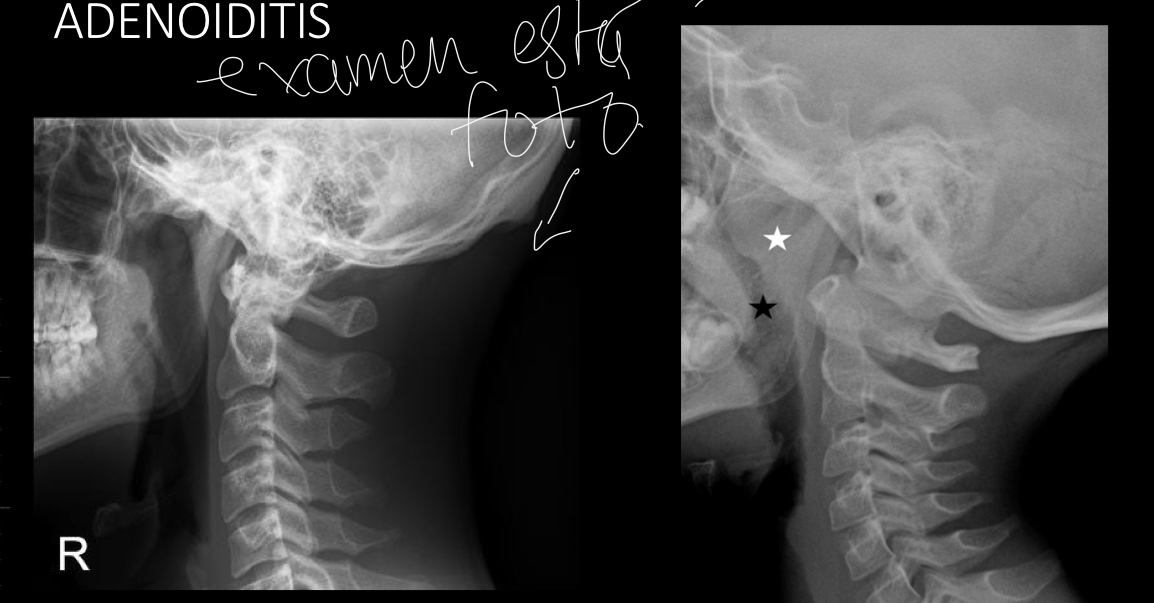

Como se pide rx

RX LATERAL DEL CUELLO CON TECNICA BLANDA

q se ve en rx

obstruccion nasofaringea

Angrosamiento adenoidea

Foto examennnnnnnn